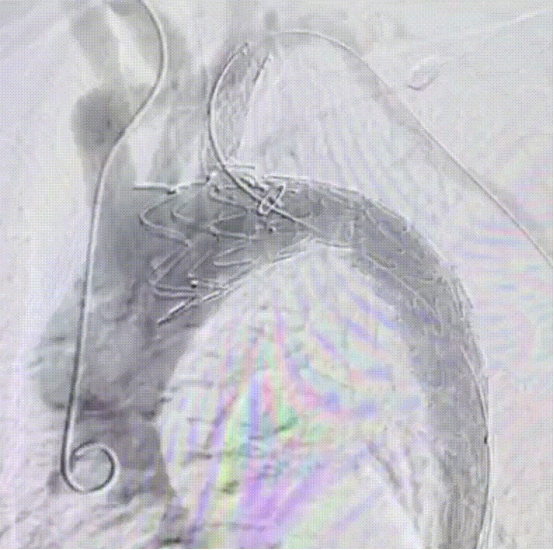

成功置入分支支架,造影显示支架塑形良好,无内漏,LSA血流通畅

远端置入裸支架